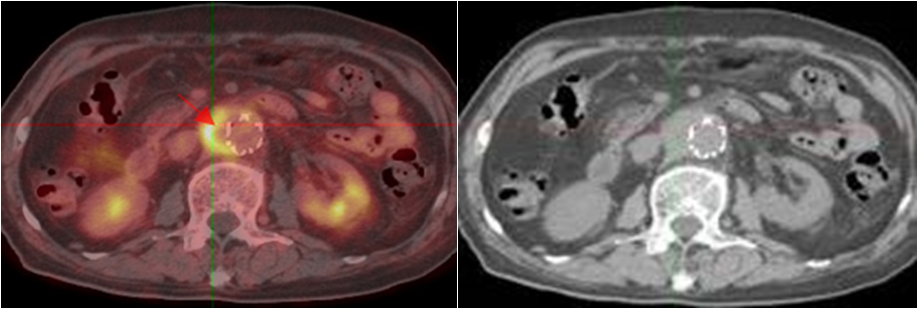

老年男性,發(fā)熱半月,全身CT未見確切異常。PET/CT示脾臟增大伴代謝明顯不均質(zhì)增高(圖2?綠箭),腹盆腔部分略大淋巴結(jié)伴帶代謝增高,診斷為淋巴瘤,病理證實(shí)為小B細(xì)胞淋巴瘤。